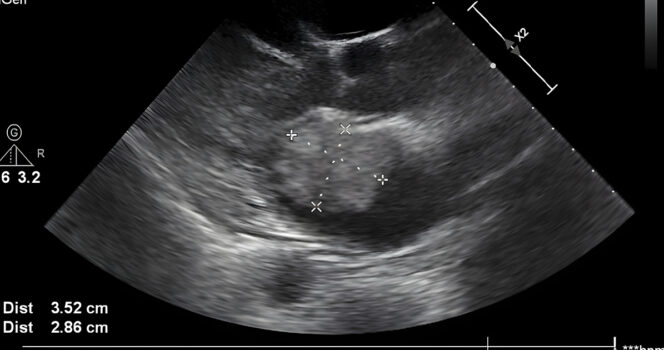

“I had an ultrasound yesterday, my youngest daughter Bailey was the first to notice it and asked me whose hand that was,” she writes in her now viral Facebook post. The post also includes a black and white image of the ultrasound, showing what she believes to be a divine presence of a giant hand cradling her son’s head. She adds: “In one of his pictures it has the appearance of a hand holding his head.”

She adds that the sight of the hand allegedly supporting Kyler’s head brought her to “tears” over “all [God] has and continues to do for me. And I couldn’t ever fathom a thought of living without [God] in my life!”